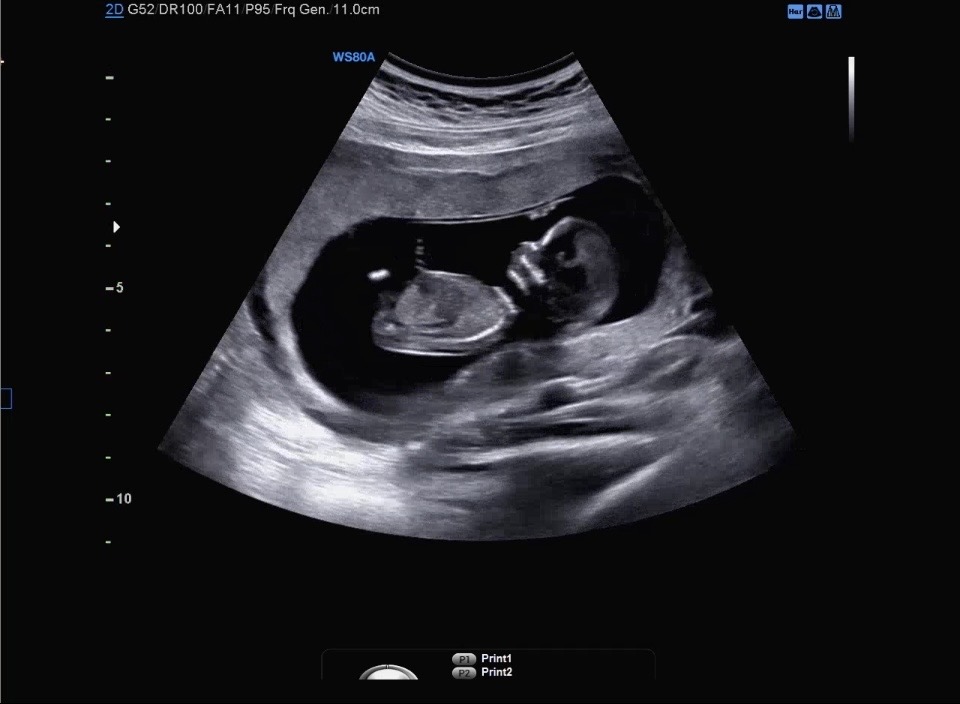

성별궁금해요

성별 너무 궁금해요ㅠㅠ

우리 아기 성별이 궁금하다면?

초음파 사진을 올리면 AI가 무료로 예측해줘요